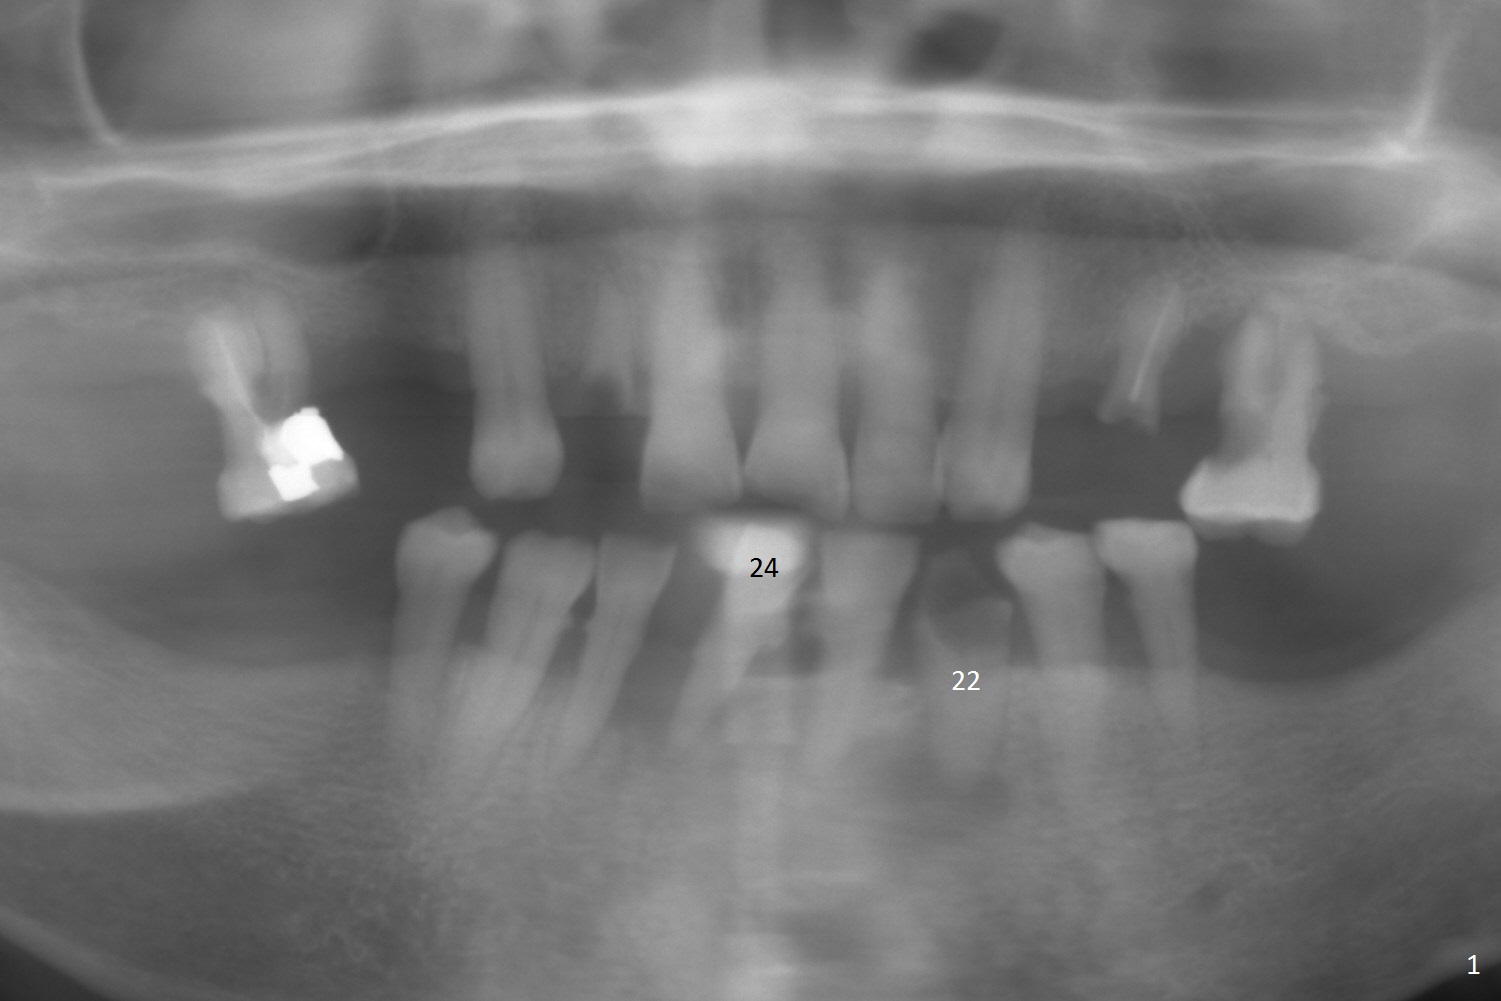

A 76-year-old healthy woman is returning for #22 and 24 implant placement (Fig.1). Since the former has a long root and the latter a narrow one, UF and 1-piece implants (straight and angled) will be placed (Fig.2), respectively. She is active. It appears that there is no osteoporosis. The bone is expected to be lower than that of a younger man. The depth at #22 should be at least 22 mm (18 mm (implant length) + 2 mm (subcrestal) + 2 mm (gingival thickness). Splinted provisional is to be fabricated at #24 and 25.